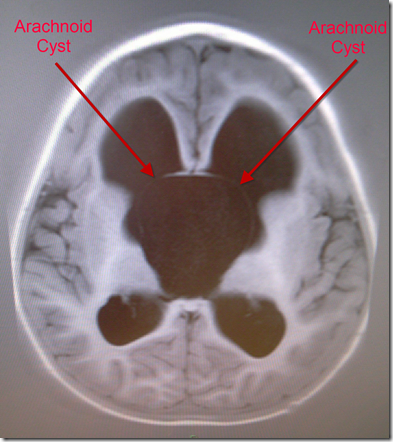

After the scan Jenifer Brown, the neurosurgeon, was round to say that the CT Scan had reviled that the fluid that was supposed to be draining was in fact pooling between his skull and his brain.

Now, although this was deemed to be bad, Jenifer had never scanned a patent after only a week, so did not know if this was just part of the normal rearranging of the brain. There is no air in your skull, so if the thin walls of Kaiden’s brain are moving around (as horrible a picture that presents) then the fluid would build there.

Jenifer opted to wait for a few days and scan him again on the Monday. If the scan showed the fluid dissipating and Kaiden was well then they would do nothing. If everything was not OK then they would operate immediately.

The took Kaiden down for a CT Scan around 12pm and we then had to wait anxiously for the results. I managed to catch a sneaky look at the scans and they looked fantastic compared to the pre-operation MRI.

When Jennifer Brown came up to see us, she said that all the fluid was being absorbed and that she could not believe the difference in Kaiden in just two short weeks. She said that we would still have little niggles for the next month or so, but that everything looked fantastic.